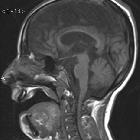

Magnetic

Resonace Imaging findings in a case of infantile Refsum disease. Sagittal T1-weighted image (b) reveals cortical atrophy and thinning of the body of the corpus callosum.